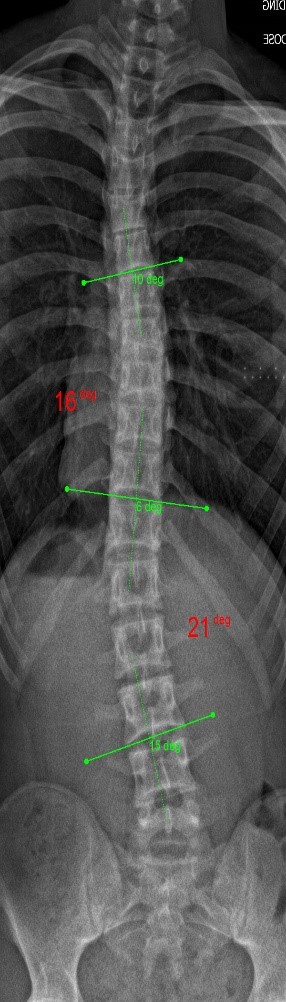

The clinical test results show that the SCN800 series is highly consistent with the X-ray, with a linear correlation of 0.94, similar results have also been published in SCI articles (Lee TT, Lai KK, Cheng JC, Castelein RM, Lam TP, Zheng YP. 3D ultrasound imaging provides reliable angle measurement with validity comparable to X-ray in patients with adolescent idiopathic scoliosis. Journal of Orthopaedic Translation. 29:51-59, 2021).

In our clinical trials and studies, we measured two angles to facilitate comparison. X-rays can actually show 3 to 4 angles, some in the neck and bottom area. Ultrasound images can also measure angles near the neck like an X-ray.

The following images compare 5 ultrasound and X-ray clinical measurement examples: